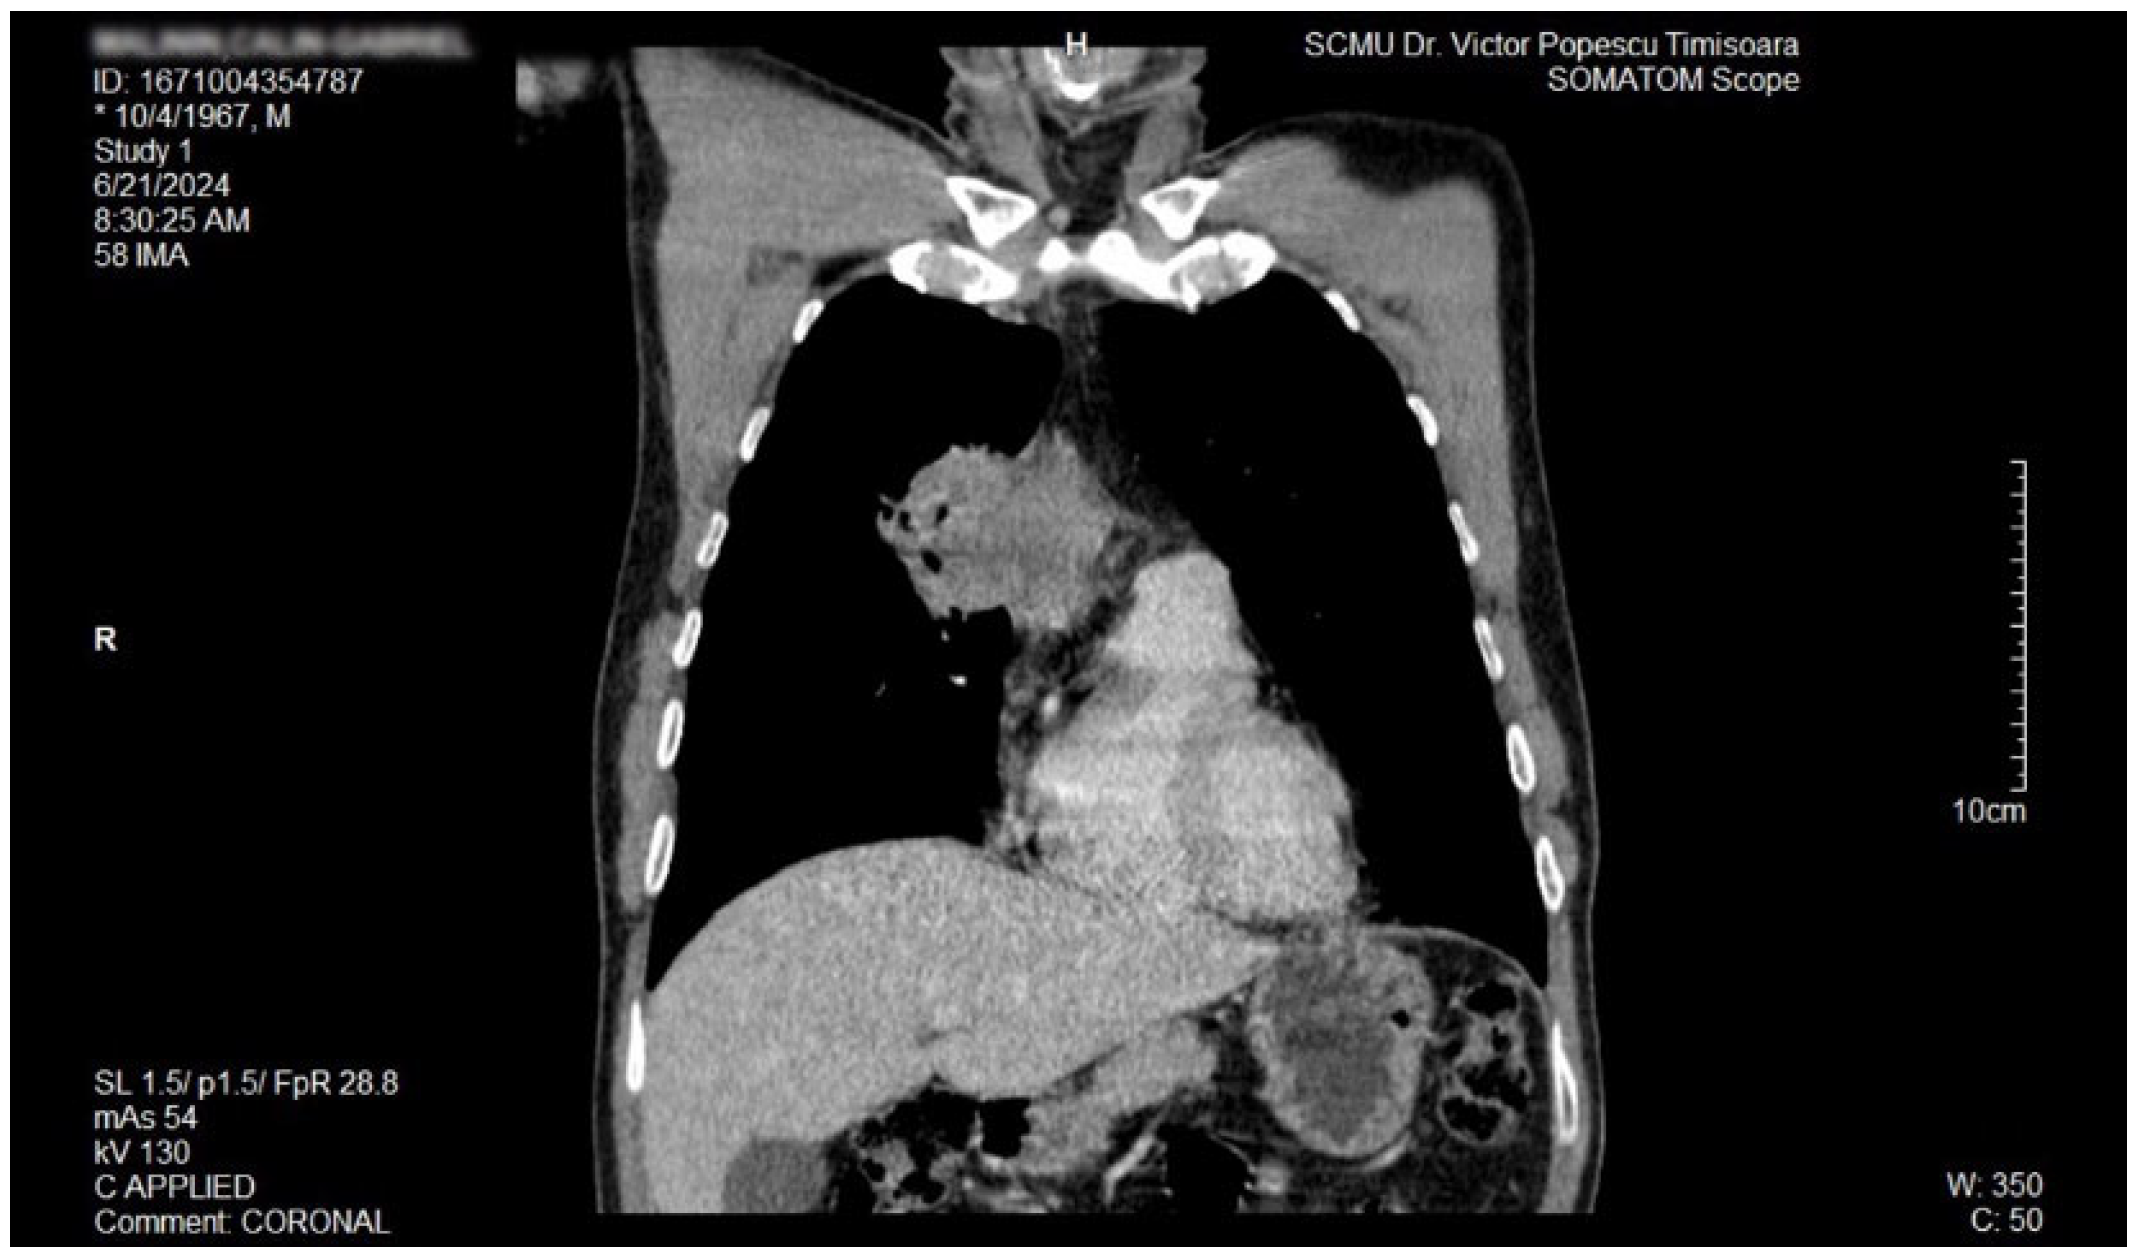

The proposal for H. pylori eradication treatment was initially postponed by the patient. However, the patient received symbiotics in order to alleviate the gut microbiota dysbiosis and also DAO supplementation, aiming at reducing the systemic effects of bacterial histamine overproduction. Further imaging studies were, however, ordered in the context of persistent, treatment-resistant pruritus that lasted for more than 6 weeks and eventually became suspicious for a malignancy. So that thorax and abdomen computed tomography (CT) were recommended and performed soon after, on 21 June 2024. As depicted in Figure 3, Figure 4 and Figure 5, a large right mid-thoracic tumoral formation with mediastinal extension of 7.8 cm/5 cm and a satellite lymph node of 7 mm placed in the anterior aspect of the upper right pulmonary lobe were discovered. The image was considered highly suspicious of lymphoma or pulmonary malignancy.

Figure 4.

Contrast thorax CT: large right midthoracic tumor with mediastinal extension (coronal view).